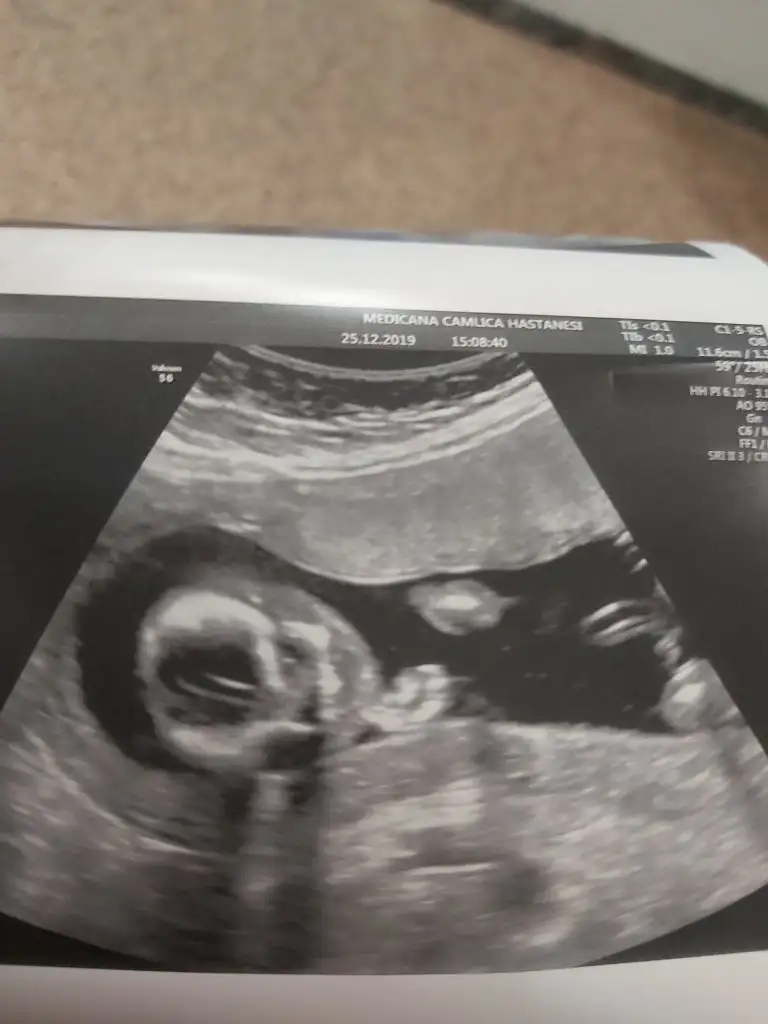

dr soylemeden siz gorun genital nub teorisi ( bebegin cinsiyeti)

Siz de yine bakarmısınız net söyledi kız diye herkes erkek demişti sizin gibi bende öyle diyordum ama ters köşe yaptı galiba bizimki çok hareketliydi 🤭🤣

• 20191225_151533.webp

20191225_151533.webp

20,5 KB · Görüntüleme: 43